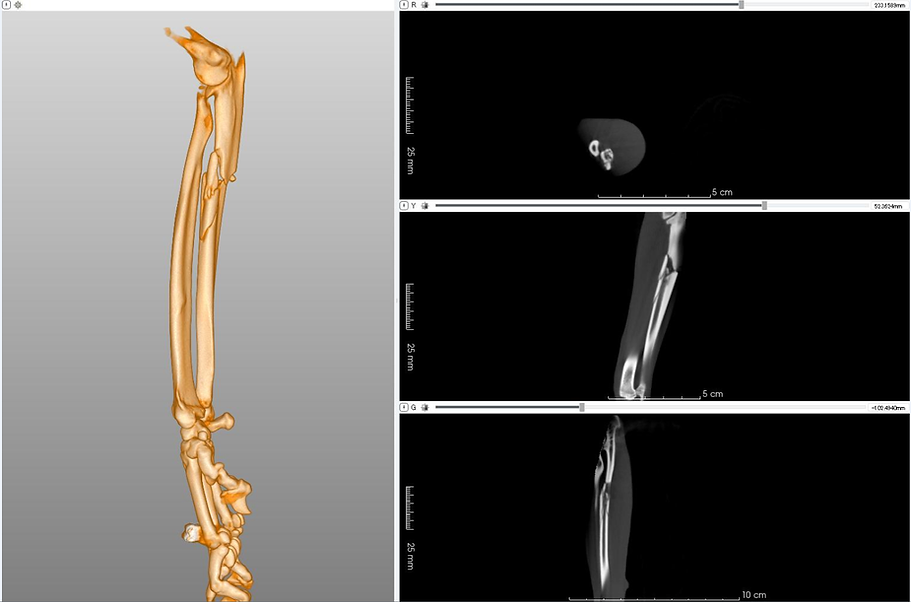

Forearm Fracture

Forearm Fracture- Post Surgery